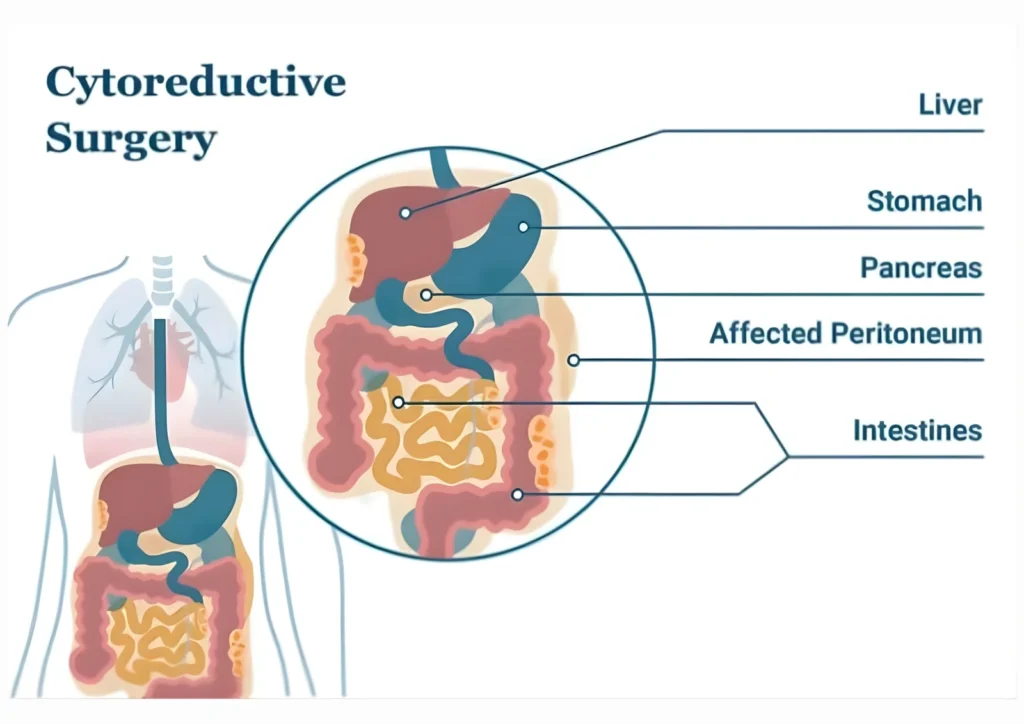

Cytoreductive Surgery (CRS)

Removal of all visible tumor deposits from the abdominal cavity

May include resection of affected organs or peritoneal surfaces

Objective is to achieve minimal or no visible residual disease

The success of HIPEC largely depends on the completeness of tumor removal during this stage.